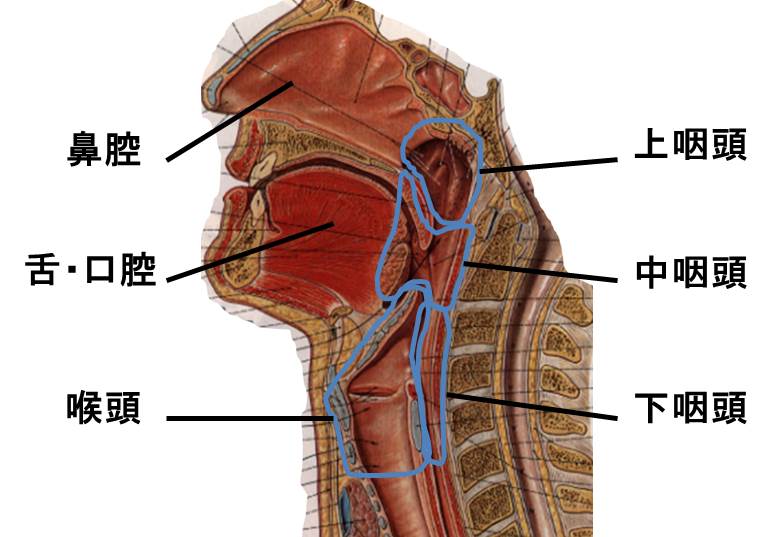

中咽頭癌 ct. 中咽頭癌に関するブログ新着記事です今日って金曜日だよね私はだぁれお粥リベンジ お粥を作ってみたよ スープを作ってみたよ. Ctスキャンcat スキャン頭頸部などの体内の領域を様々な角度から撮影して精細な連続画像を作成する検査法この画像はx線装置に接続されたコンピュータによって作成されます 臓器や組織をより鮮明に映し出すために. 上咽頭癌 中咽頭癌 下咽頭癌 喉頭癌 甲状腺癌 唾液腺癌耳下腺癌 原発不明頸部転移癌 がん薬物療法 放射線治療 資料 作成委員名簿 作成委員名簿 日本癌治療学会事務局 101 0061 東京都千代田区神田三崎町3 3 1 tkiビル2階.

咽頭がんを早期発見するには そもそも咽頭とはどこのこと Helc

咽喉頭異常感 小児科 内科 皮膚科 耳鼻咽喉科 アレルギー科の